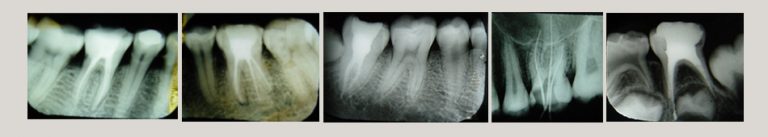

X-Rays After Root Canal Treatment